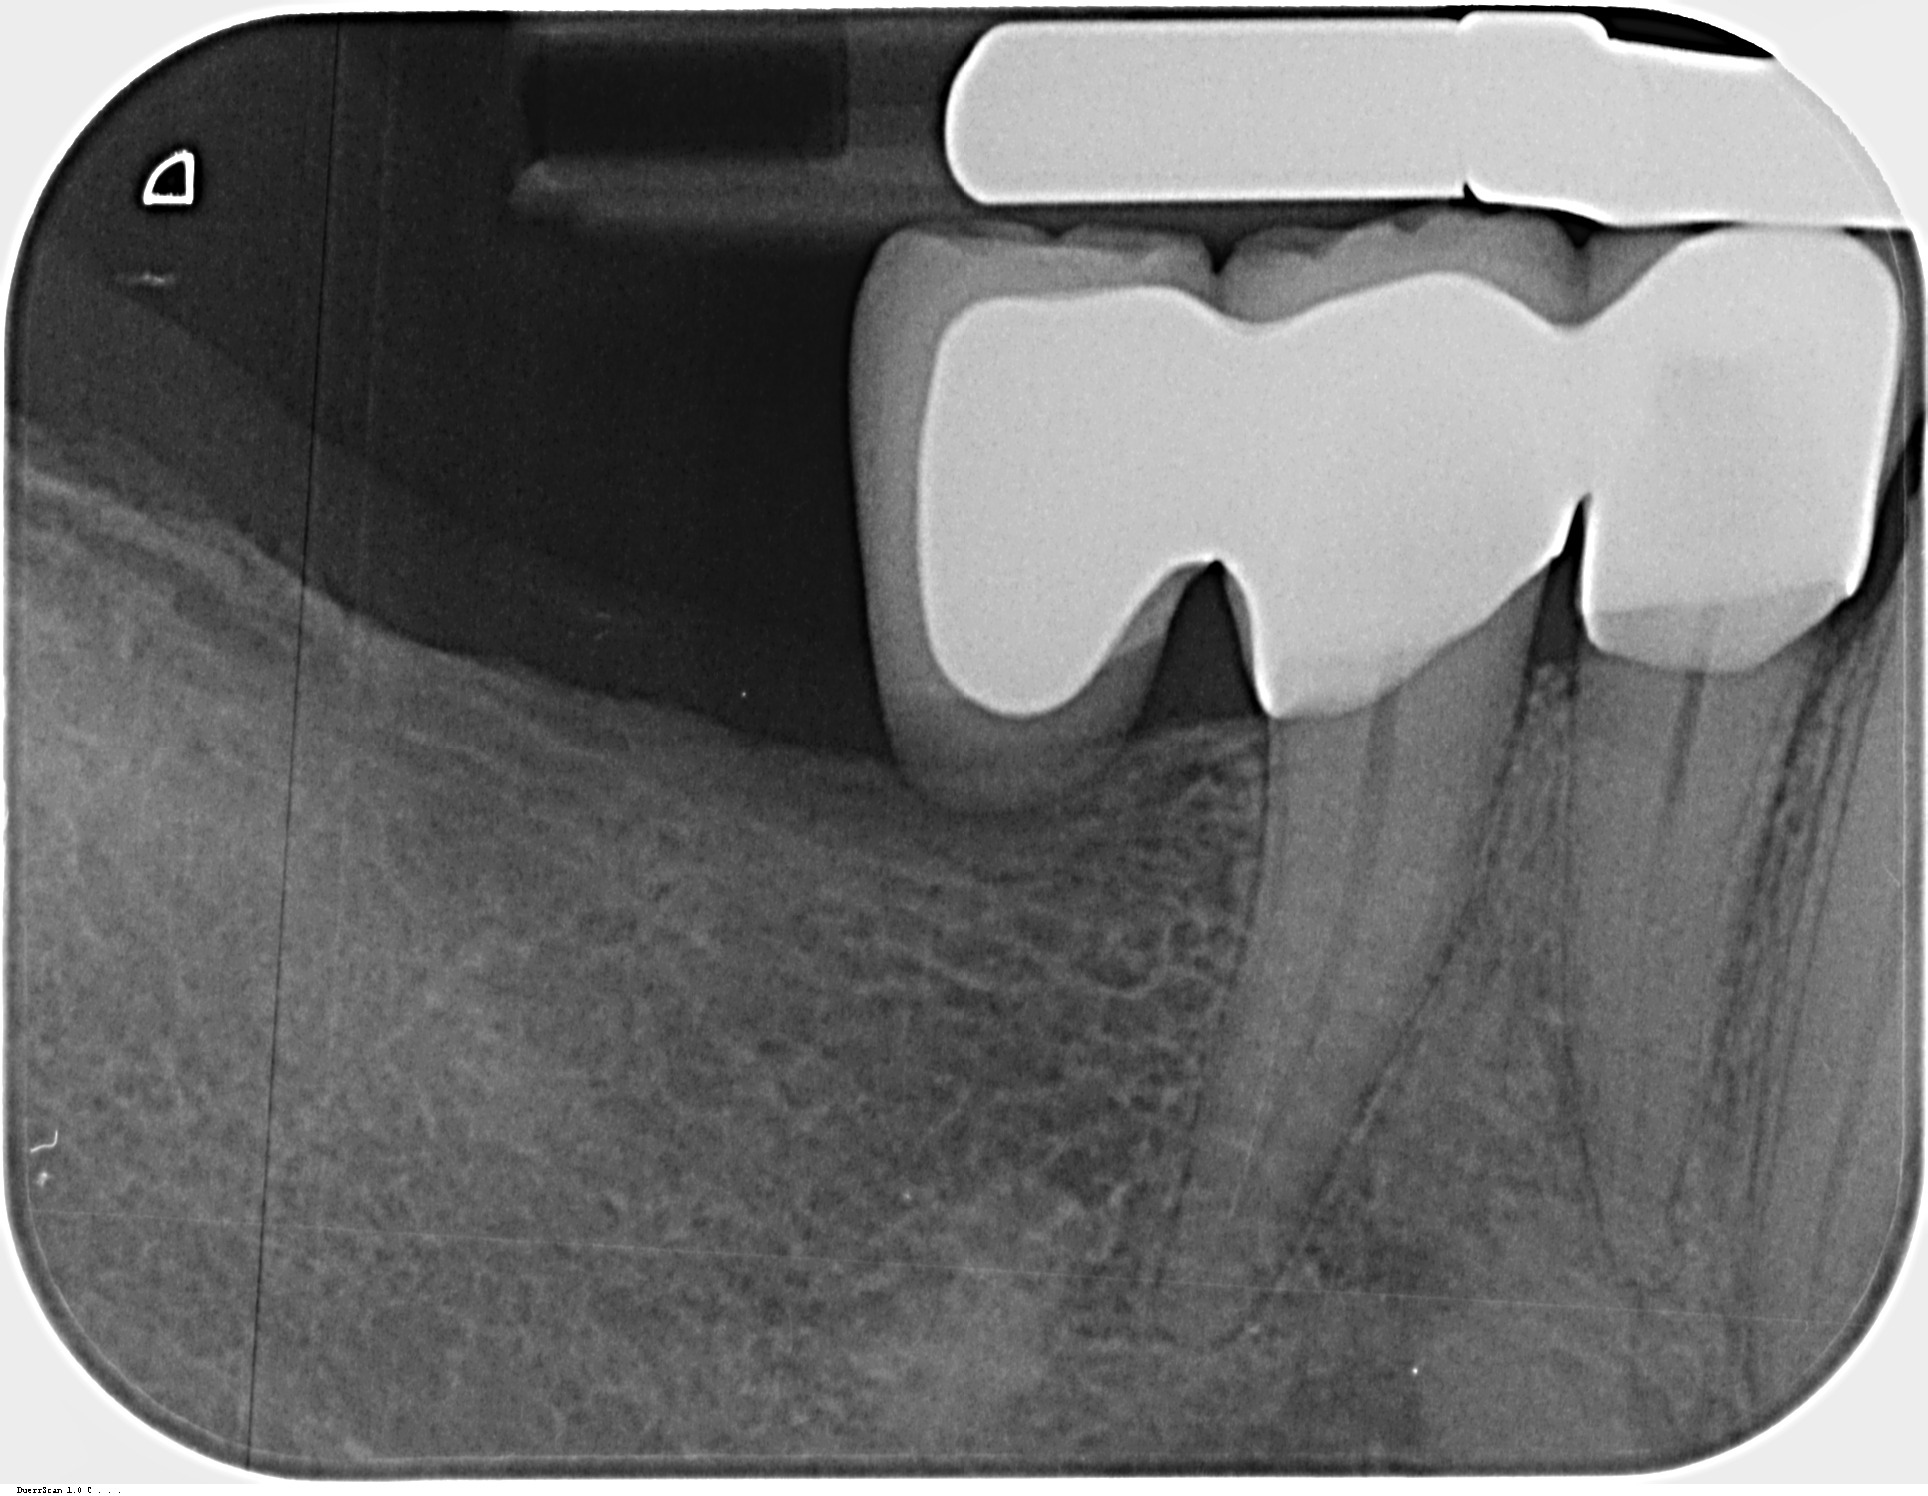

Im Februar wurde bei mir diese Freiendbrücke in Regio 44–46 eingesetzt, die seit Beginn Probleme macht – auch bereits das Provisorium – Druckgefühl, Entzündungen und Schmerzen beim Kauen. Ich war etliche Male zur Nachbesserung, doch die Beschwerden blieben bestehen.

Ich habe dann den Zahnarzt gewechselt. Dieser hat vor 2 Monaten die Brücke endgültig zementiert, das entzündete Zahnfleisch dabei entfernt und den Zwischenraum zwischen 44-45 erweitert, sodass ich mit einer Interdentalbürste reinigen kann. Doch es bestehen weiterhin Schmerzen beim Kauen, besonders bei härteren Speisen.

die brücke wirkt vorne undicht.

wenn sie das sein sollte, dann neu machen.